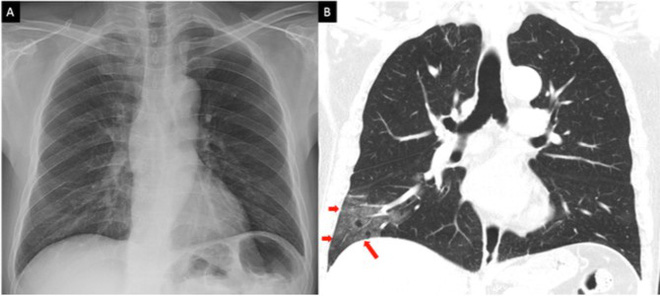

Mới đây, Tiến sĩ Nguyễn Văn Vĩnh Châu, Giám đốc Bệnh viện Bệnh Nhiệt đới TP HCM cho biết siêu âm phổi của nam bệnh nhân 43 tuổi thấy đông đặc toàn bộ bên phổi trái, đông đặc 1/3 dưới phổi phải.

Không phải bất cứ ai nhiễm virus cũng đều có triệu chứng và tổn thương phổi. Tuy nhiên, nghiên cứu có khoảng 25% bệnh nhân khi nhiễm virus, đầu tiên là virus Sars-CoV-2 xâm nhập tế bào, hình thành nên ổ virus; tiếp theo là gây rối loạn hệ miễn dịch (ví dụ hội chứng bão cytokine); và cuối cùng là gây tổn thương phổi trong đó có đông đặc phổi hay còn gọi là gan hoá phổi.

Đối với đại dịch Covid-19 qua các báo cáo, nghiên cứu, khám nghiệm tử thi của bệnh nhân Covid-19 đều thấy bệnh nhân có biểu hiện của đông đặc phổi cấp và tử vong vì suy hô hấp cấp. Đây được xem là "sát thủ" của bệnh nhân Covid-19.

Bác sĩ Nam cho biết bình thường nhu mô phổi xốp nhưng khi nhu mô phổi bị viêm, các phế nang xung huyết chứa đầy dịch tiết, tỷ trọng nhu mô phổi tăng được biểu hiện lâm sàng bằng hội chứng đông đặc.

Với những bệnh nhân bị áp xe phổi là tình trạng mưng mủ của nhu mô phổi bị viêm. Nguyên nhân do vi khuẩn gây mủ ưa khí hoặc kỵ khí, X-quang sẽ thấy mờ ở phổi hoặc nhiều ổ áp xe. Tới giai đoạn thoát mủ có thể thấy hình hang với mực nước ngang các ổ áp xe.

Đông đặc phổi còn xuất hiện ở bệnh nhân bị nhồi máu động mạch phổi. Tắc một nhánh động mạch phổi thường gặp ở bệnh nhân có tình trạng máu dễ đông như hẹp van hai lá sau khi mổ, mổ ở vùng tiểu khung, một số người sau đẻ.

Đối với hội chứng đông đặc phổi cấp tính đa phần người bệnh đều khó phục hồi và chỉ 10 % có khả năng phục hồi lại sau quá trình chạy tim phổi ngoài nhân tạo do hội chứng đông đặc phổi cấp. Nếu bệnh nhân may mắn không chết, phổi của họ cũng bị tổn thương vĩnh viễn - bác sĩ Nam cho biết.